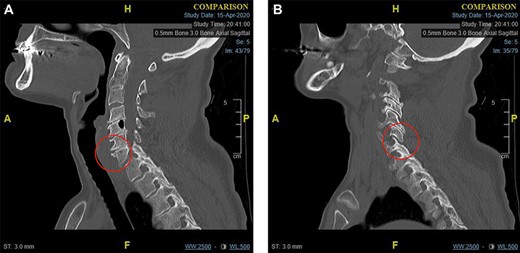

There is an acute fracture of the antero-superior osteophyte of the body of C7 (Fig. 2a). There is also opening of the cervical facet at C6/7 (Fig. 2b). There were no fractures of the vertebral bodies. It can also be appreciated that there is significant degenerative change between C4 and C7.

(a) Para-midline sagittal CT scan of the cervical spine at the time of first presentation showing a fracture of the antero-superior osteophyte of C7 (indicated with a circle). and (b) Para-midline sagittal CT scan of the cervical spine at the time of first presentation showing opening of the C6/C7 facet joint (indicated with a circle).